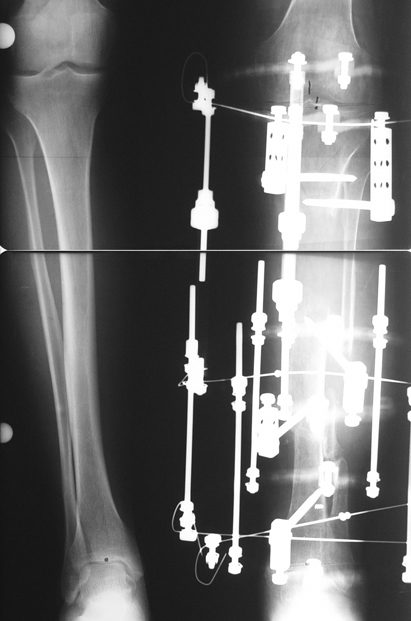

Uygun radikal debridman tüm nekrotik kemik ve yumuşak dokuların çıkartılmasını gerektirir, ve sıklıkla uzuvda instabiliteye neden olur. Kalan kemik ve yumuşak doku defektinin bir şekilde fiksasyonu ve rekonstrüksiyonu gereklidir. İlizarov’un ortaya koyduğu distraksiyon osteogenezi yöntemi, kaynamanın elde edilmesi, deformitenin düzeltilmesi, bacak boy eşitsizliğinin giderilmesi ve segmental defektlerin rekonstrükte edilmesi için başarıyla kullanılmaktadır.

Eksternal fiksatör ile geçen süre (eksternal fiksasyon indeksi), gereken distraksiyon miktarına bağlıdır ve bu süre boyunca bazı komplikasyonlarla karşılaşılabilir. Distraksiyon dönemi sona erdikten sonra, distraksiyon süresinin iki katını aşan konsolidasyon döneminde hastalar eksternal fiksatörü zorlukla tolere edebilirler. Yeterli konsolidasyon sağlanmadan eksternal fiksatör çıkartılırsa ise kırıklar, deformite ve kısalık oluşabilir. Hastanın fiksatör ile birlikte geçirdiği sürenin azaltılması ve böylece hasta konforunun ve aktivite düzeyinin arttırılması için intramedüller çivi üzerinden uzatma yöntemi uygulanmaktadır. Bu yöntemde distraksiyon dönemi sona erdiğinde kemiğin içindeki çivi statik olarak kilitlenmekte ve eksternal fiksatör çıkartılmaktadır. Stabilizasyon intramedüller çivi tarafından sağlandıktan sonra konsolidasyon dönemi gerçekleşmektedir. Bu şekilde hem eksternal fiksatörün uzun süre kalmasından hem de erken çıkartılmasından kaynaklanan komplikasyonların önüne geçilmektedir.